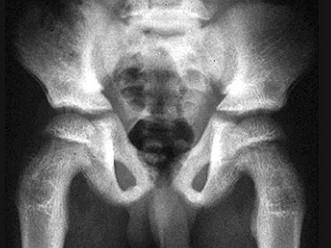

问题 男,6岁,来自居住于干旱地区,腰背疼痛四肢关节酸痛,请结合图像,选出最可能的诊断 ( )

选项 A、髋关节结核 B、甲状旁腺功能亢进 C、畸形性骨炎 D、石骨症 E、氟骨症

答案 E